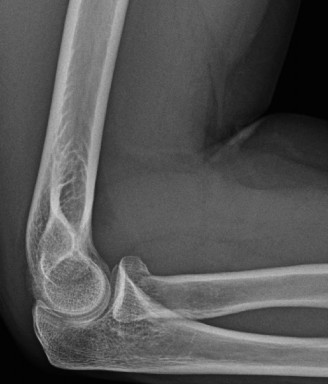

Understand common complications associated with performing surgery for scapulothoracic bursitis? CASE 33 A 42-year-old female presents to the office for follow up after sustaining a minimally displaced radial head fracture 3 months prior. She states she was initially treated in long-arm splint by the ER and did not follow up with an orthopaedic surgeon until now. Per her report, she removed the splint 4 weeks after the injury, but did not move her elbow due to pain. She now has no pain but is unable to reach that hand to her face or head. The remaining history is significant for previous ulnar nerve surgery for which she is unable to provide details. On physical examination, her upper extremity is normal except for limited flexion/extension, measured to be 80 to 50 degrees by goniometer. In addition, she has a well-healed surgical incision about the medial elbow, consistent with a previous surgery on her ulnar nerve. Her images are shown (Figs. 2–82 to 2–84).

Figure 2–82

Figure 2–83

Figure 2–84

What is the diagnosis?

Discussion

The correct answer is (A). Classification of post-traumatic elbow stiffness allows for better understanding of the disease and allows the clinician to treat the underlying cause of the joint contracture. Intrinsic causes include: any problem within the joint such as incongruency, loose bodies, or severe osteoarthritis. Extrinsic causes include capsular tightness, muscle contracture, heterotopic ossification, and skin contractures. Early is defined as within 6 months of the injury while late is considered to be greater than 6 months after the injury. Patients that present in the early time frame have a significantly better chance at having a good result both from nonoperative and operative treatment.